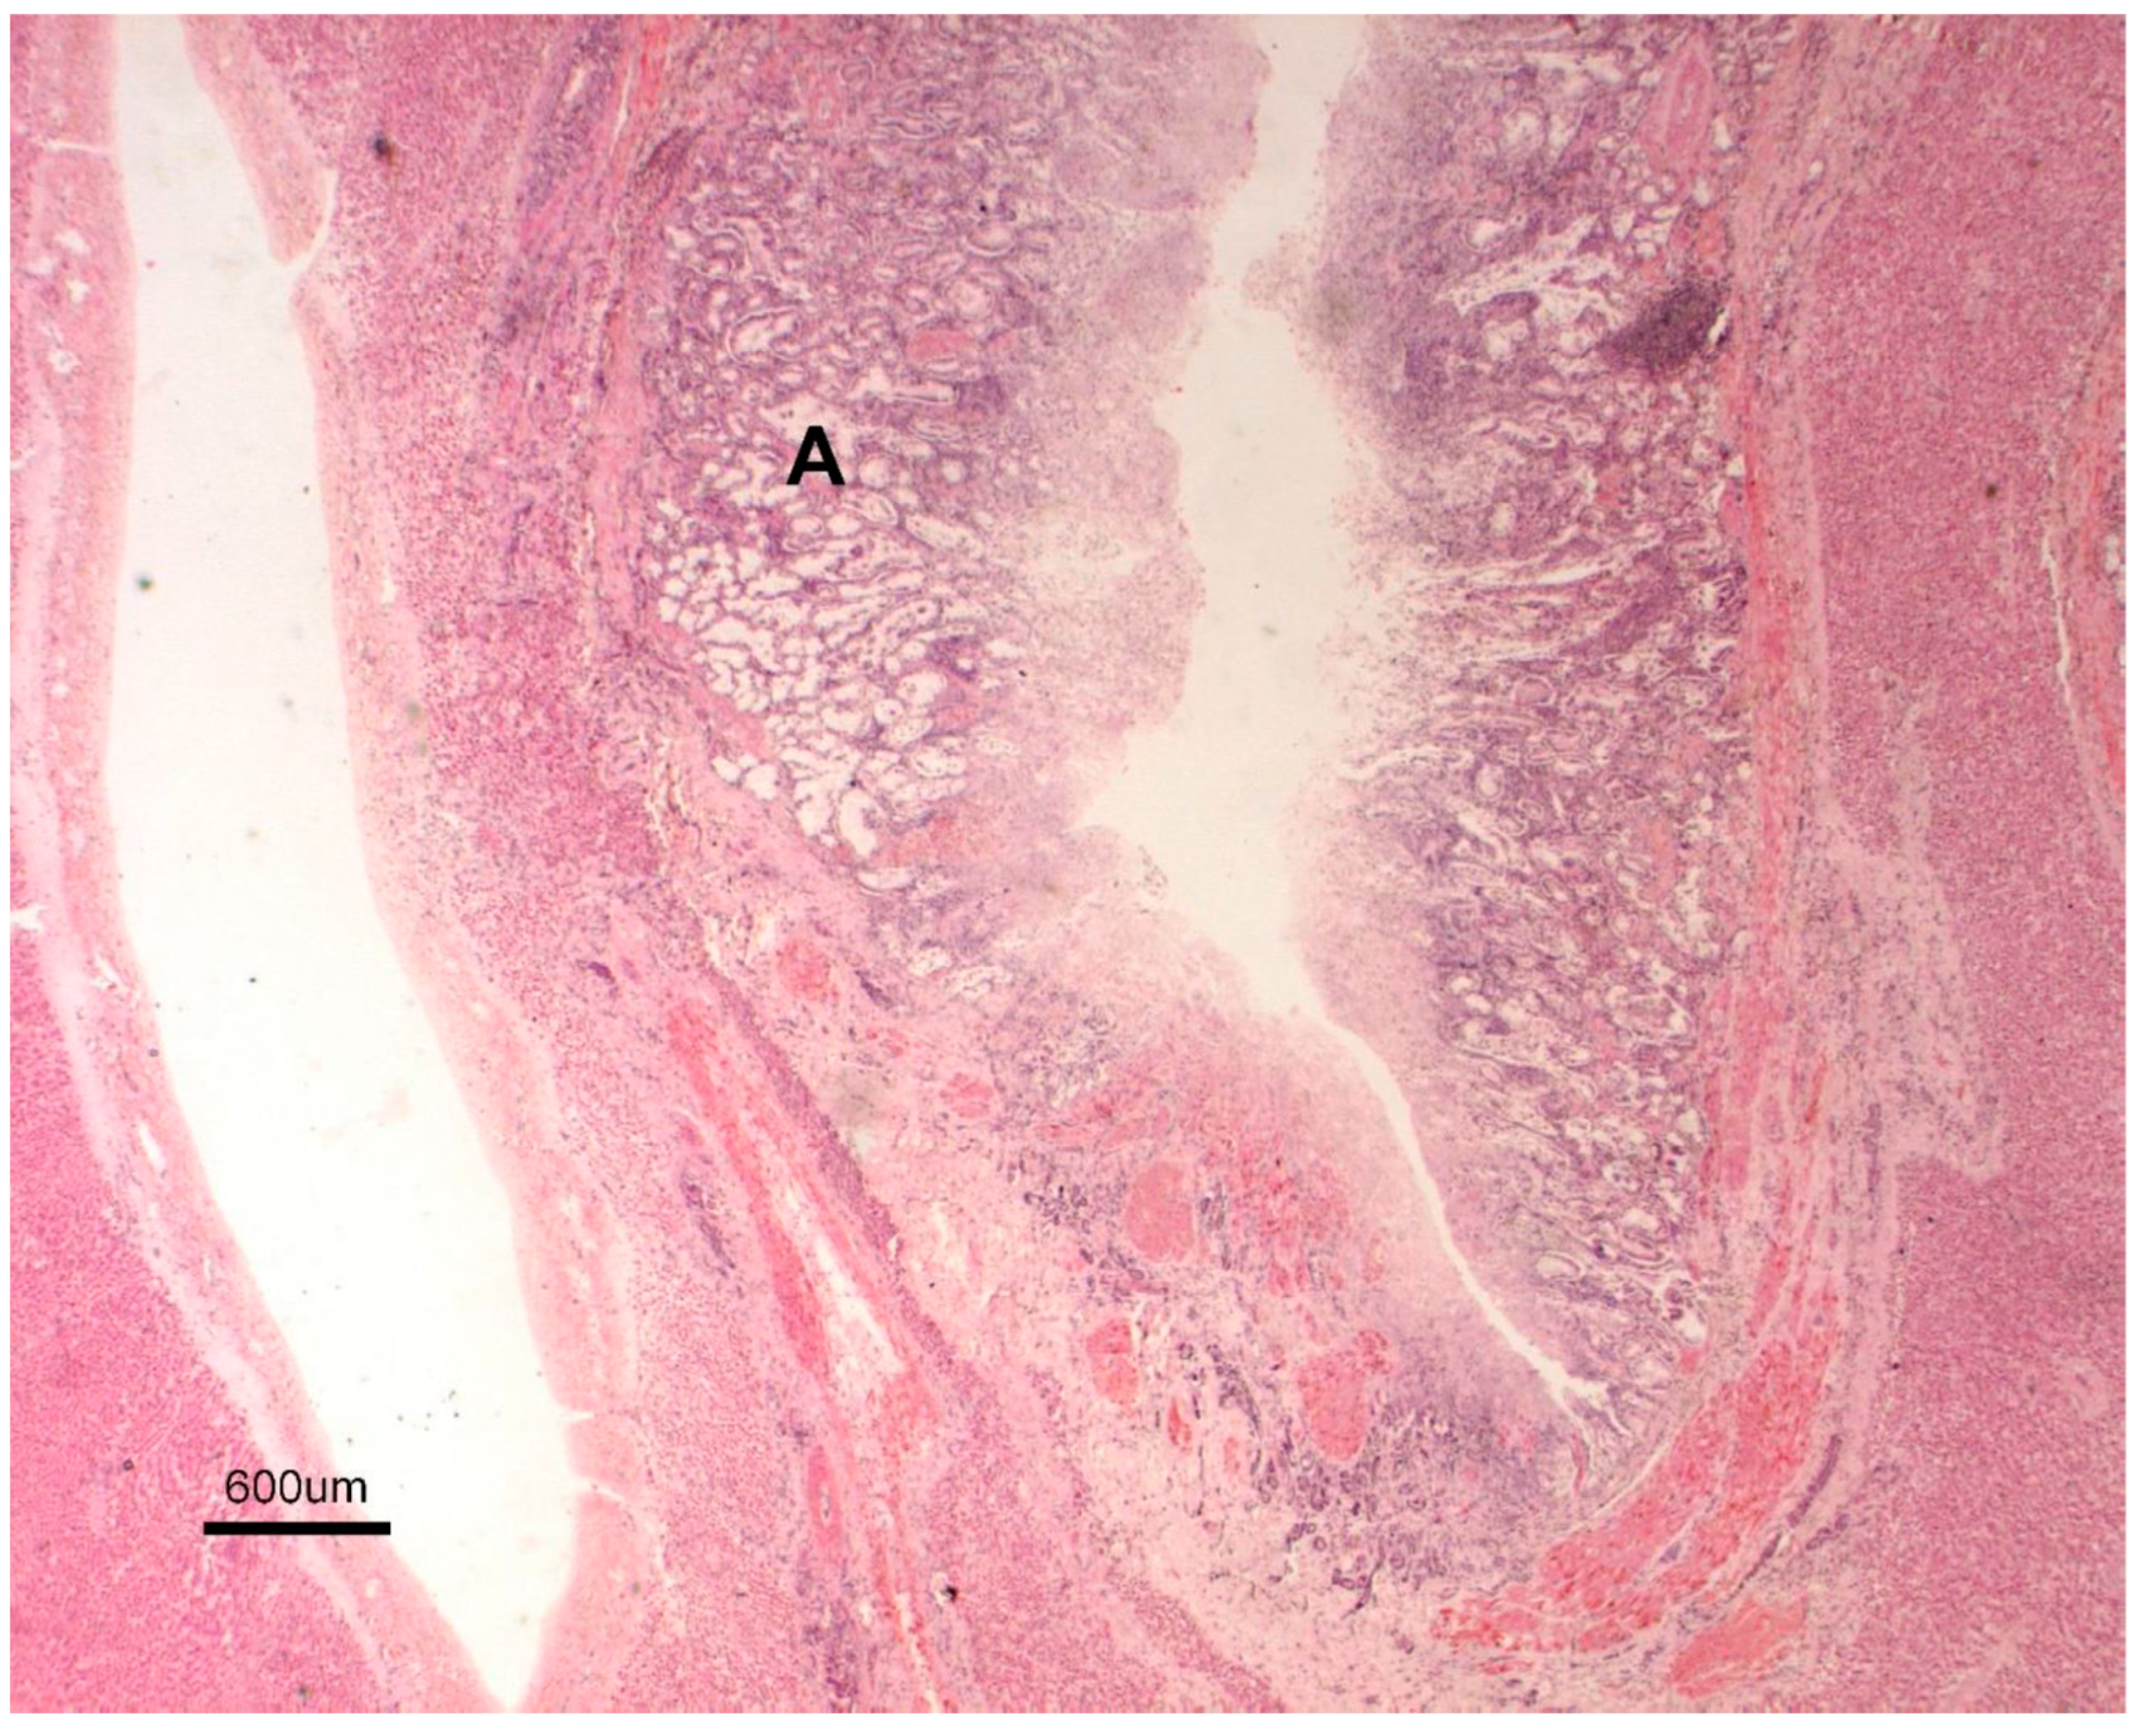

3.1. Necropsy